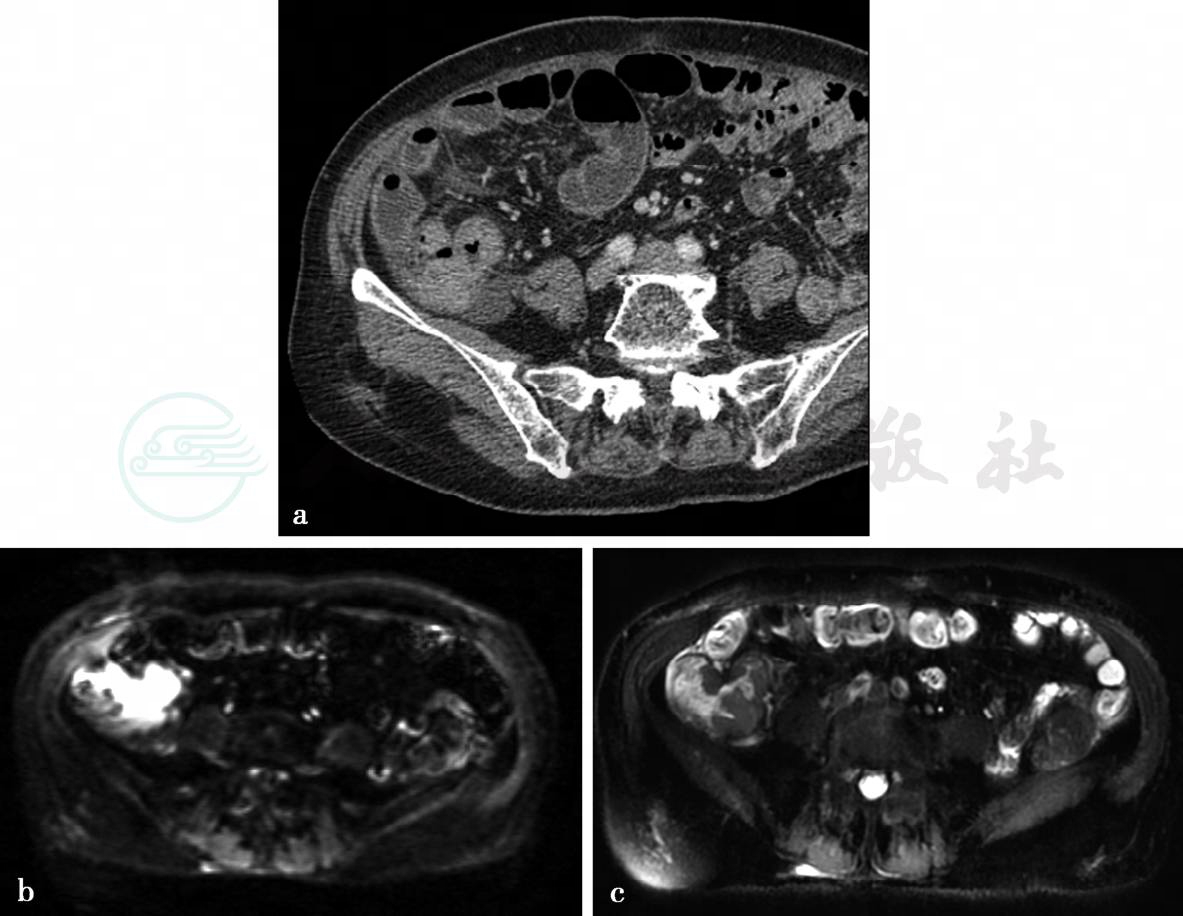

病例10:CT增强扫描及MRI平扫及弥散加权图(升结肠癌)。

图1 图1a,CT增强静脉期图。图1b、c,分别为轴位T2WI及DWI图。升结肠肠壁增厚,轻度强化,MRI上呈稍长T2信号,DWI上为高信号